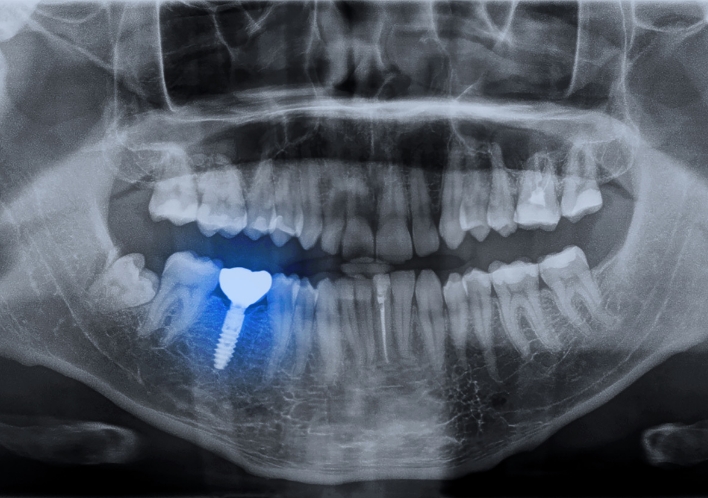

インプラント治療は、単に失った歯の見た目や機能を補うだけでなく、その後の生活の質を向上させるための治療法です。顎の骨にチタン製の人工歯根(フィクスチャー)を埋入し、その上に人工歯(上部構造)を装着することで、まるでご自身の歯のような自然な噛み心地と安定性を回復させます。周囲の健康な歯に負担をかけることなく、顎の骨に直接固定されるため、「第二の永久歯」とも呼ばれています。

現在のインプラント治療は、CTやシミュレーションを用いた精密な診断と治療計画により、その安全性と成功率が確立されています。

先進設備による精密な診断

高精細なCT画像で、歯やあごの骨、神経や血管の位置を立体的に把握します。

神経や血管を傷つけず、正確なインプラント埋入を可能にします。

事前シミュレーションの徹底

CT画像をコンピューターに取り込み、インプラントの埋入位置、角度、深さを事前にシミュレーションします。

歯科医師の経験や技術だけでなく、客観的なデータに基づいた、より正確で安全な治療計画を立てます。

インプラント埋入手術

安全・正確に埋入できるよう、角度や深度、位置をサポートするサージカルガイドを用いて、インプラントをあごの骨に埋入します。

局所麻酔により痛みを感じることはほとんどありません。埋入の翌日から通常の生活ができます。

患者様によっては手術を2回に分けるケースもあります。

1回目でインプラント体を埋入しあごの骨との結合定着を確認し、2回目でアバットメントを連結します。